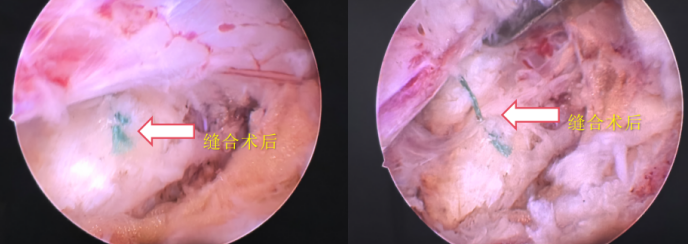

骨伤一科副主任罗继介绍,从以下两个临床案例,可清晰说明其适用场景、核心条件与临床价值。

52岁教师王女士(化名),因长期伏案致L4-5椎间盘突出,右腿麻木影响行走。经MRI检查后,骨伤一科团队评估其符合缝合条件。手术中,通过UBE双通道摘除髓核,再用特制针缝合纤维环,未增加切口或延长手术时间。术后3天下床,麻木减轻,2个月返岗,复查显示纤维环愈合良好。

36岁工人赵先生(化名),搬重物后突发L5-S1椎间盘突出,伴下肢放射痛。虽纤维环撕裂,但评估发现破口紧邻神经根、边缘钙化无弹性、直径超10mm(缝合易开裂),故仅行UBE髓核摘除,术后需避免剧烈活动、练核心肌群并定期复查。

髓核除后、手术结束前,先内镜确认破口情况,再用专用器械缝合,最后内镜检查闭合效果。